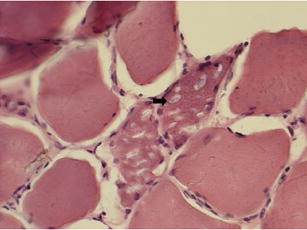

The following day the histopathology results of the muscle biopsy were available, which read as ‘vacuolated myopathy - probable acid maltase deficiency disorder’ (see Fig. 1). The patient was transferred to a tertiary center for possible enzyme replacement therapy. Four weeks later the results of the biochemical enzyme assay were obtained and showed low acid maltase levels, 0.57 micromol/min/gram1.74-9.98, confirming the diagnosis of primary acid maltase deficiency.

Vacuolated myopathy: Biopsy of the patient’s deltoid muscle on a hematoxylin-eosin stain showing intracytoplasmic vacuoles.